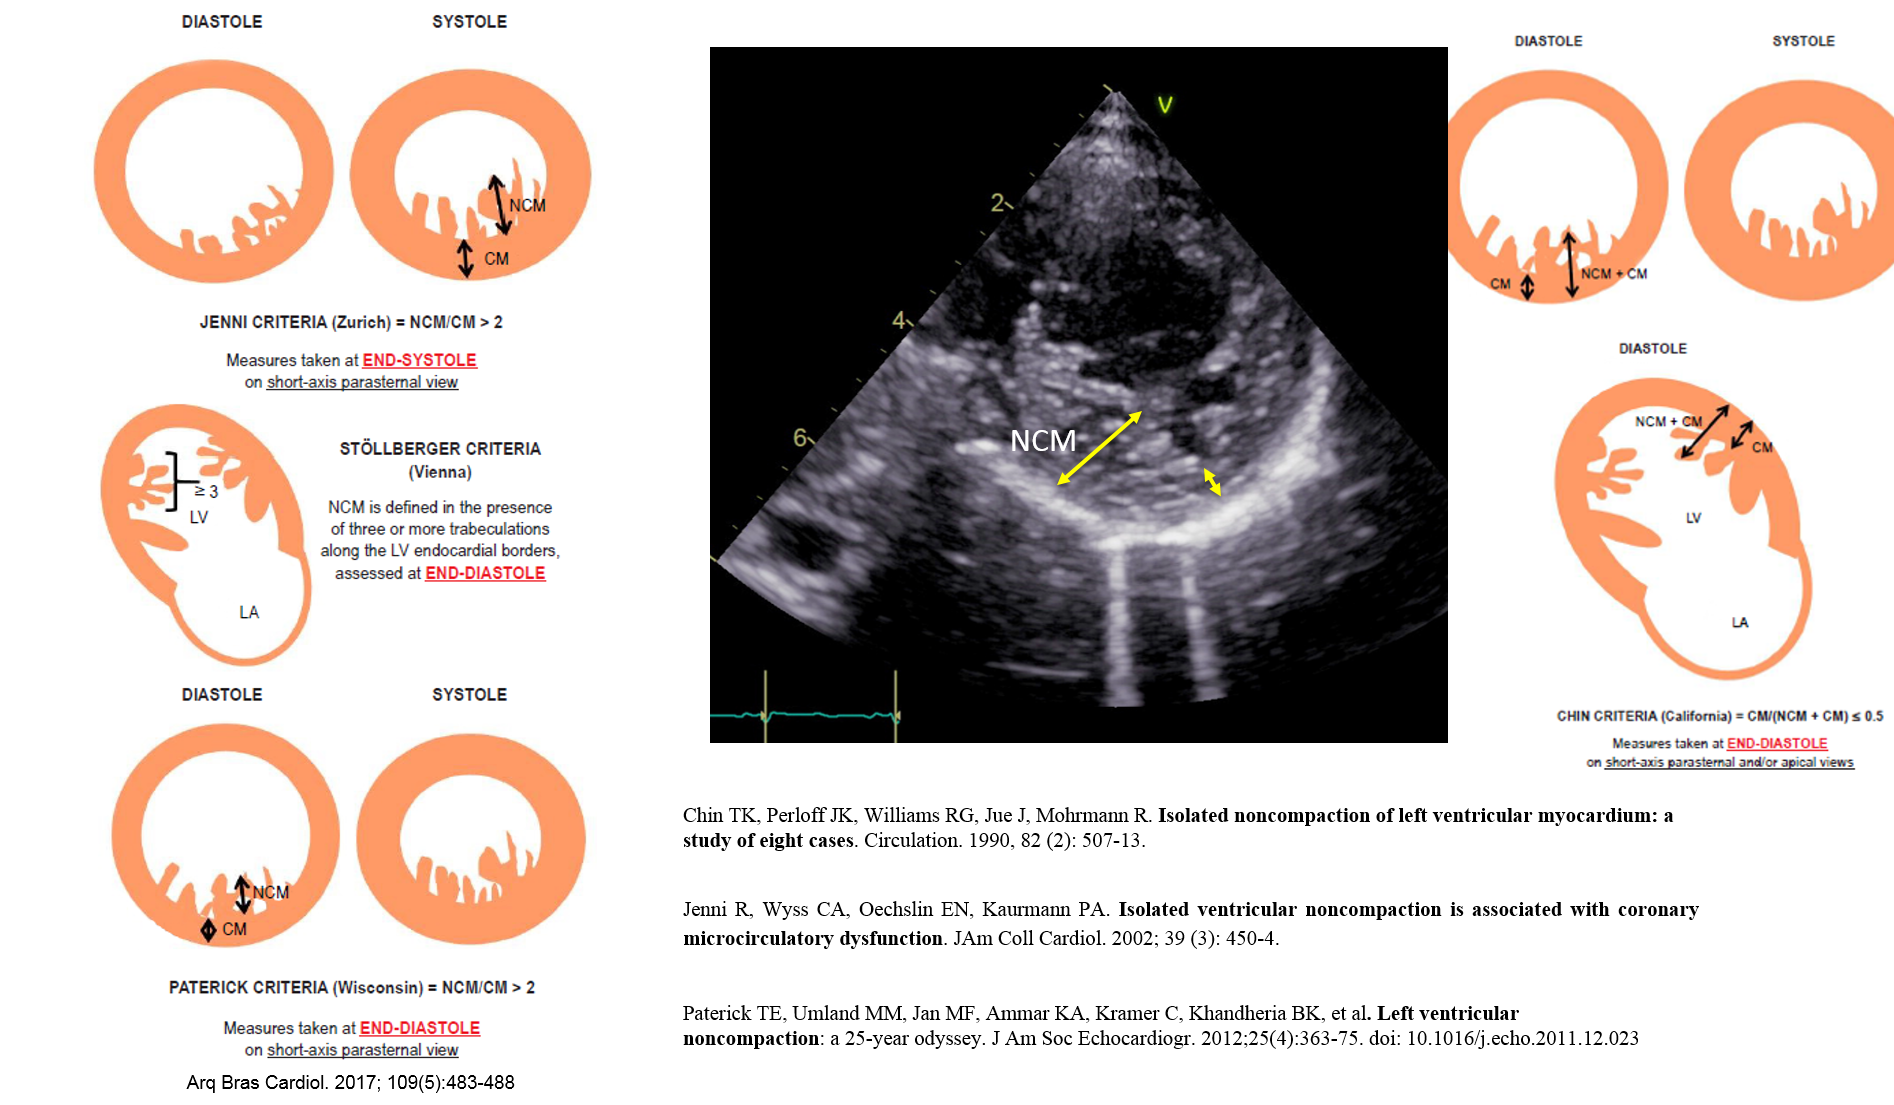

CM recognized as dystinct type in 2006, normally LV is more affected (and is called LVNC) but both ventricle could be abnormal, LVNC is a structural abnormality of the left ventricular myocardium of uncertain etiology and it is speculated that it results from a disturbed compaction process during early development of the LV myocardium. Neuromuscular disorders and chromosomal defects are noted (as example, Barth’s syndrome). It is recommended that first degree relatives of patients with LVNC be investigated for LVNC. Diagnosed is done by Echo (different criteria are used for the diagnosis, see Figure below) that shows prominent trabeculae, intertrabeculae recesses and 2 distinct layers of myocardium (compacted and no compacted). although cardiac MRI is the gold standard test for diagnosis.